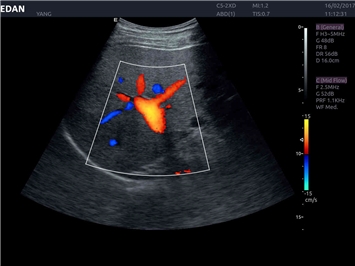

EDAN Acclarix LX4

Расширьте свои представления. Использование усовершенствованной платформой Acclarix система LX4 обеспечивает непревзойденную четкость изображений и интеллектуальный рабочий процесс для всех пользователей, являясь при этом наиболее экономичным решением.

EDAN Acclarix LX4 представляет собой инновационную ультразвуковую систему, построенную на усовершенствованной платформе Acclarix. Сочетание высокого качества визуализации с интеллектуальным рабочим процессом делает эту систему оптимальным выбором для клиник, ценящих эффективность и экономичность.

Трехмерная реконструкция ЦДК:

Да

Цветовой допплер: